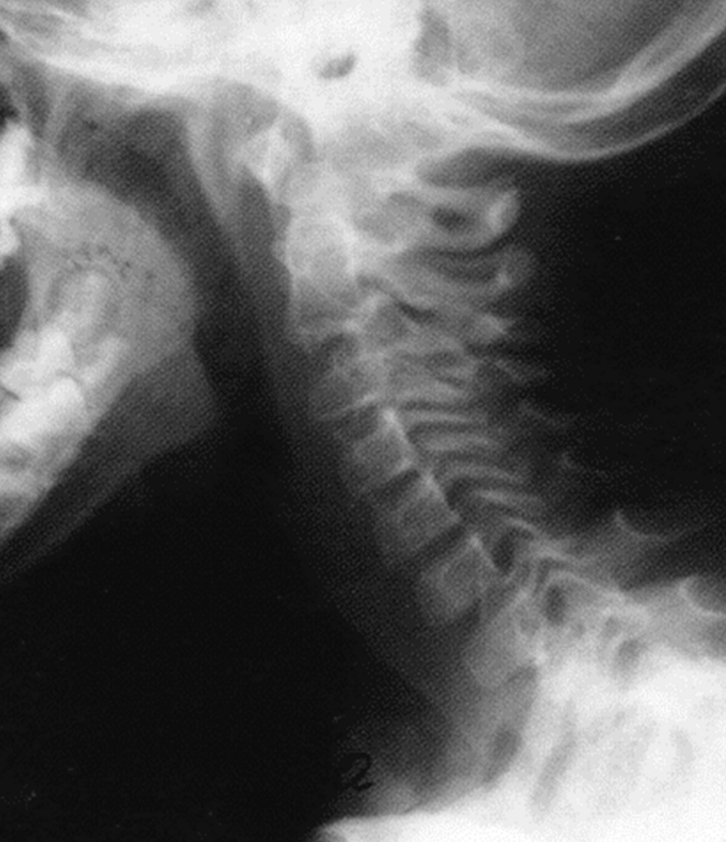

Боли в шее

и головные боли -